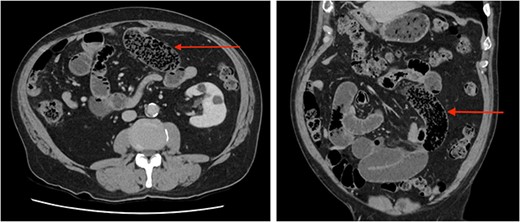

A bowel obstruction was suspected, the patient was resuscitated with intravenous fluids, a nasogastric tube was inserted, and a computed tomography (CT) with intravenous (IV) contrast performed. On CT, multiple dilated loops of small bowel were identified with a transition point in the mid-abdomen (Fig. 1). The radiologist reported faecalization of small bowel contents at the transition which was thought to be consistent with an adhesional small bowel obstruction. The patient was admitted for a trial of conservative management. In the next 48 hours, he had failed to resolve and developed increasing pain and evolving peritonitis.

Abdominal CT scan axial (left) and coronal (right) images demonstrating ‘faecalization’ (arrow) of small bowel content.

Clinical features of SBO due to bezoar are indistinct from other causes such as adhesions. Most patients presenting acutely with symptoms of SBO will have a CT scan as they are rapid, non-invasive, and readily available. CT scans facilitate diagnosis and identification of underlying cause, and complications such as strangulation or perforation. Features of SBO on CT are dilated loops of small bowel proximally with collapsed loops distally, in 82% of cases there will be faecalization of bowel content [11]. On CT, faecalization is recognized as solid appearing content, typically distal within the small bowel, intermixed with air near the site of obstruction, in our patient both were identified. Interestingly, these features are similar to those observed with bezoar. A bezoar is oval or round, of soft-tissue density and also filled with air, found at the transition point [12]. Features that may favour a bezoar are a well-defined shape, an encapsulating wall, and a lesion in the stomach similar to the obstructing mass [12]. Unsurprisingly, diagnostic accuracy of bezoar is limited and misdiagnosis common [6]. Regarding our case, in retrospect our patients’ typical findings of faecalization were the bezoar. The similarities in these findings highlight the importance a thorough history and careful assessment of imaging where a bezoar is suspected, especially as these patients typically require surgery.